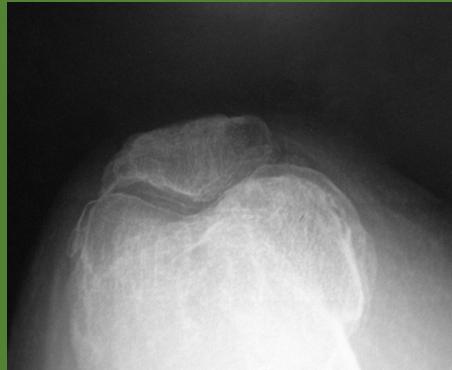

Imaging Studies

- Standard Radiographs:

- Both knees AP standing views (weight-bearing)

- Lateral views of both knees

- Skyline view (patellofemoral assessment)